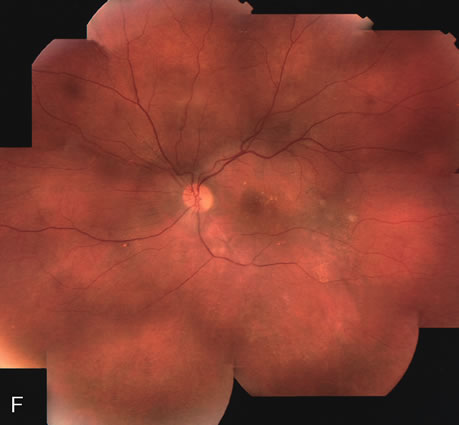

Fig. 20. A. Red-free photograph of a 20-year-old patient with sudden loss of vision to the level of 20/200. There is exudative, neurosensory macular detachment, a few hemorrhages, and lipid exudates. B. Fluorescein angiography reveals the presence of classic choroidal neovascularization (CNV), which appears to be juxtafoveal (<200 μ from fixation). Given the size of the CNV and its proximity to the fovea, it was decided to treat the patient with photodynamic treatment (PDT). C. Red-free photograph of the same eye 2 weeks after PDT; there is increased subretinal exudation D. Fluorescein angiography demonstrates that the CNV is still actively leaking. E. Red-free photograph 4 weeks after PDT demonstrates further increase in the size of the neurosensory macular detachment, subretinal hemorrhages, and lipid exudation. F. Fluorescin angiography reveals that the CNV has extended under the fovea. Given the young age of the patient, an inflammatory component of the neovascular process was suspected. It was decided to give a posterior, subtenon injection of triamcinolone acetonide, 40 mg/1 mL. G. Two weeks after steroid treatment there is partial reabsorption of the subretinal fluid. H. Fluorescein angiography demonstrates contraction of the CNV. I. Four weeks after injection of triamcinolone there is further reduction in the degree of neurosensory detachment; vision had improved to 20/60. J. Fluorescein angiography demonstrates that the CNV is smaller and less active (less leakage).

FA is needed to assess response to laser photocoagulation of a CNV and to diagnose recurrent membranes.51,54 The authors generally obtain angiograms 2 weeks, 1 month, 3 months, and 6 months after treatment. The risk of recurrence is greatest during the first 3 months, and the patient, who often has decreased vision due to prior neurosensory detachment, may be asymptomatic. FA is also needed to evaluate the results of PDT. In the original protocol of the Verteporfin in Photodynamic Therapy (VIP) and Treatment of Age-Related Macular Degeneration with Photodynamic Therapy (TAP) studies, a fluorescein angiogram was obtained every 3 months, and if there was persistent leakage from the CNV PDT was applied again (see Fig. 1820).60